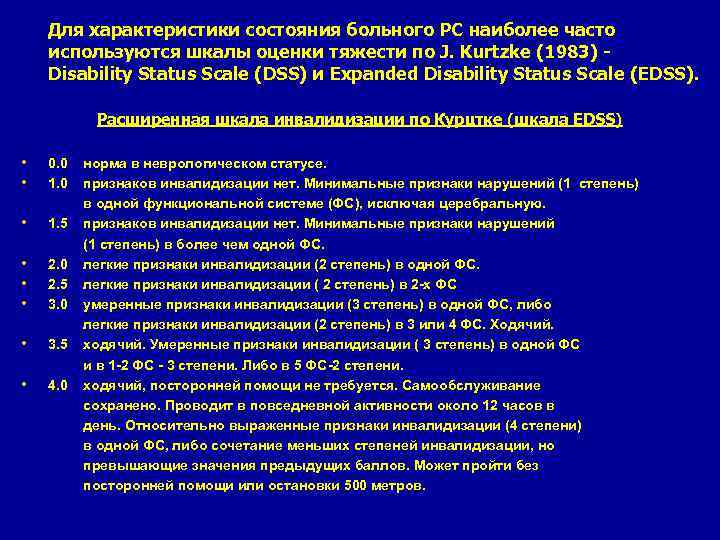

Для характеристики состояния больного PC наиболее часто используются шкалы оценки тяжести по J. Kurtzke (1983) - Disability Status Scale (DSS) и Expanded Disability Status Scale (EDSS). Расширенная шкала инвалидизации по Курцтке (шкала EDSS) • • 0. 0 норма в неврологическом статусе. 1. 0 признаков инвалидизации нет. Минимальные признаки нарушений (1 степень) в одной функциональной системе (ФС), исключая церебральную. • 1. 5 признаков инвалидизации нет. Минимальные признаки нарушений (1 степень) в более чем одной ФС. • 2. 0 легкие признаки инвалидизации (2 степень) в одной ФС. • 2. 5 легкиe признаки инвалидизации ( 2 степень) в 2 -х ФС • 3. 0 умеренные признаки инвалидизации (3 степень) в одной ФС, либо легкие признаки инвалидизации (2 степень) в 3 или 4 ФС. Ходячий. • 3. 5 ходячий. Умеренные признаки инвалидизации ( 3 степень) в одной ФС и в 1 -2 ФС - 3 степени. Либо в 5 ФС-2 степени. • 4. 0 ходячий, посторонней помощи не требуется. Самообслуживание сохранено. Проводит в повседневной активности около 12 часов в день. Относительно выраженные признаки инвалидизации (4 степени) в одной ФС, либо сочетание меньших степеней инвалидизации, но превышающие значения предыдущих баллов. Может пройти без посторонней помощи или остановки 500 метров.